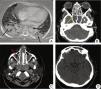

The image examination of the sinuses revealed extensive shadowing of the maxillary, frontal, sphenoid, and ethmoid sinuses, which was attributed to invasive sinusitis (Fig. 6). The otorhinolaryngology team performed a biopsy of the sinuses and a direct examination of the nasal cavity. Surgical treatment through debridement was not possible due to persistent thrombocytopenia and lesion angioinvasion. Histopathology and direct examination were similar to the findings of the skin lesion. She also had extensive bilateral diffuse pulmonary infiltrate consistent with invasive pneumonia.

A, Chest tomography showing a pattern of parenchymal consolidation with intermingled air bronchograms, notably in the posterior region of the pulmonary fields (black arrows). (B, C, and D) CT scan of the sinuses showing diffuse veiling of the paranasal sinuses, characterized by material with soft tissue density filling the maxillary (red arrow), sphenoid (yellow arrow), and frontal sinuses (blue arrow), and the ethmoidal cells (white arrow).